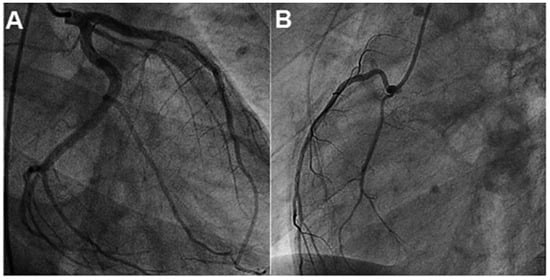

A patient with Morbus Behçet was admitted with severe symptomatic aortic regurgitation caused by aortitis that mimicked infective endocarditis. After aortic valve replacement and antibiotic treatment, regurgitation and systemic inflammation recurred....